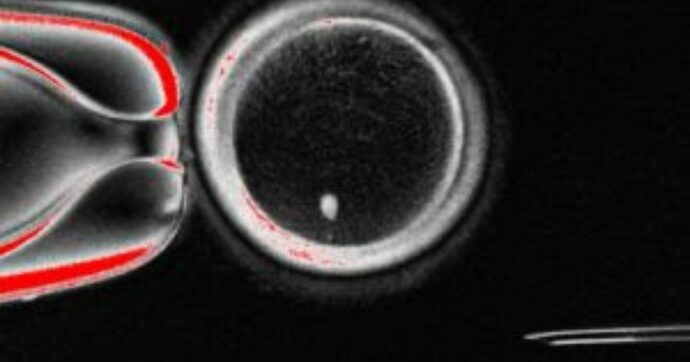

In questo lavoro, i ricercatori forniscono la prova di concetto di un approccio alternativo, che consiste nel trasferimento nucleare di cellule somatiche. Gli scienziati hanno utilizzato ovociti umani prelevati da donatrici e li hanno privati del loro nucleo. In questi citoplasmi sono stati inseriti nuclei di fibroblasti, ottenuti da cellule somatiche. Una volta trasferiti, i cromosomi somatici si sono condensati e hanno formato strutture simili a fusi meiotici. Le unità biologiche si sono quindi differenziate in ovociti funzionali. Il processo ha permesso agli scienziati di ottenere 82 ovuli pronti per la fecondazione. Lo studio proof-of-concept fornisce la prova che la riprogrammazione cellulare potrebbe essere una strada praticabile negli esseri umani per affrontare l’infertilità. Tuttavia, precisano gli scienziati, la possibilità di future applicazioni cliniche richiede ulteriori ricerche per garantire l’efficacia e la sicurezza di questa metodologia.

In effetti, riportano gli scienziati, dopo la fecondazione con spermatozoi, gli ovociti non procedevano autonomamente nello sviluppo. Per superare questo ostacolo, gli esperti hanno applicato una attivazione artificiale con impulsi elettrici ed un inibitore selettivo delle chinasi, che ha permesso la separazione dei cromosomi. Il sequenziamento ha rivelato che in media lo zigote manteneva circa 23 cromosomi, mentre gli altri venivano espulsi in un corpuscolo.

Foto: Ovocita SCNT umano con fuso visibile (punto luminoso all’interno) prima della fecondazione

Credito: laboratorio Mitalipov